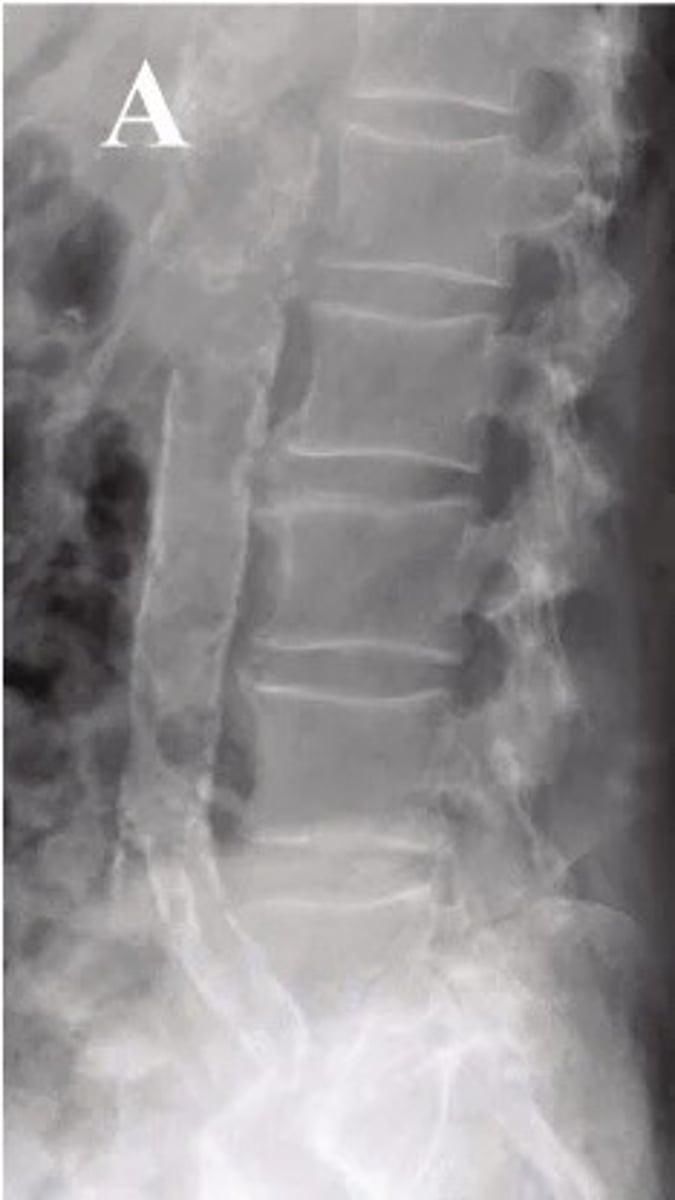

calcified abdominal aorta

what pathology is present?